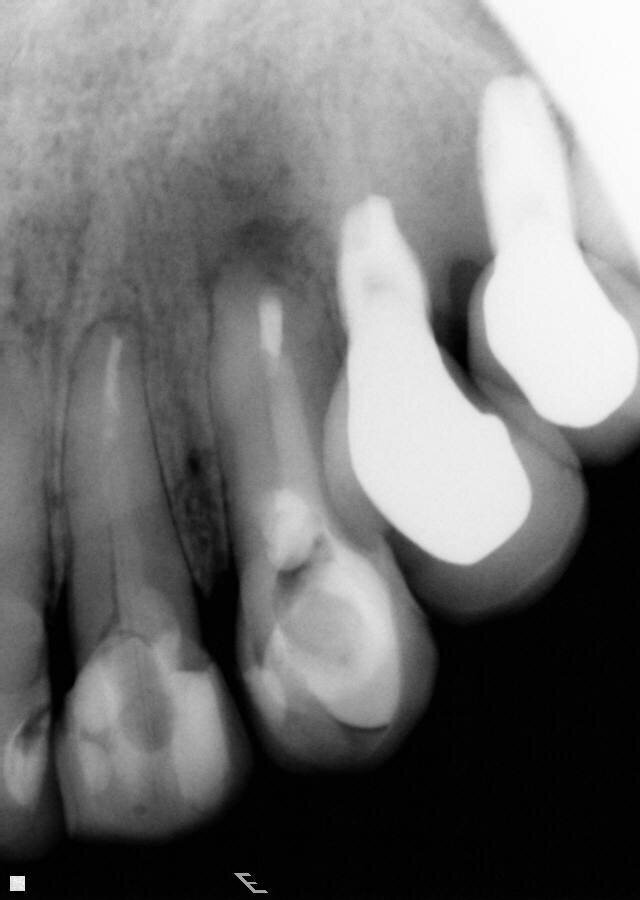

Fig. 1: A cone beam computed tomography was performed for diagnosis and to establish a treatment plan. (Photos/Provided by Renato Interliche, Douglas Giordani Negreiros Cortez and Clauber Romagnoli)

After clinical and radiographic examination, a cone beam computed tomography was performed for better diagnosis and to establish the treatment plan for the involved tooth (Fig 1).